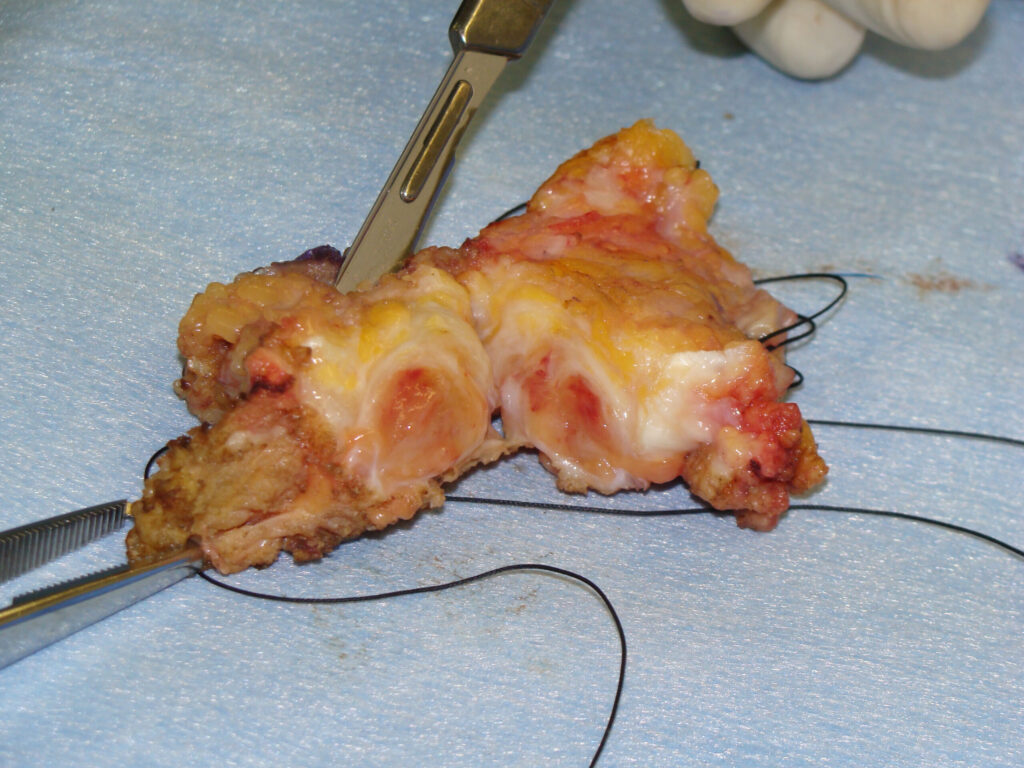

Gross Pathology

Synovial sarcomas are usually circumscribed, round or multilobular masses

They may grow to >15 cm, but on average measure 3 to 5 cm in greatest diameter since many occur in the foot and ankle

Can be described as yellow to gray-white

The less differentiated variants often grow more rapidly and tend to be poorly circumscribed, with multiple areas of hemorrhage, necrosis, and cystic formation

Biphasic form is composed of both epithelial-cell and spindle-cell components in equal proportions (Fig. 6-8)